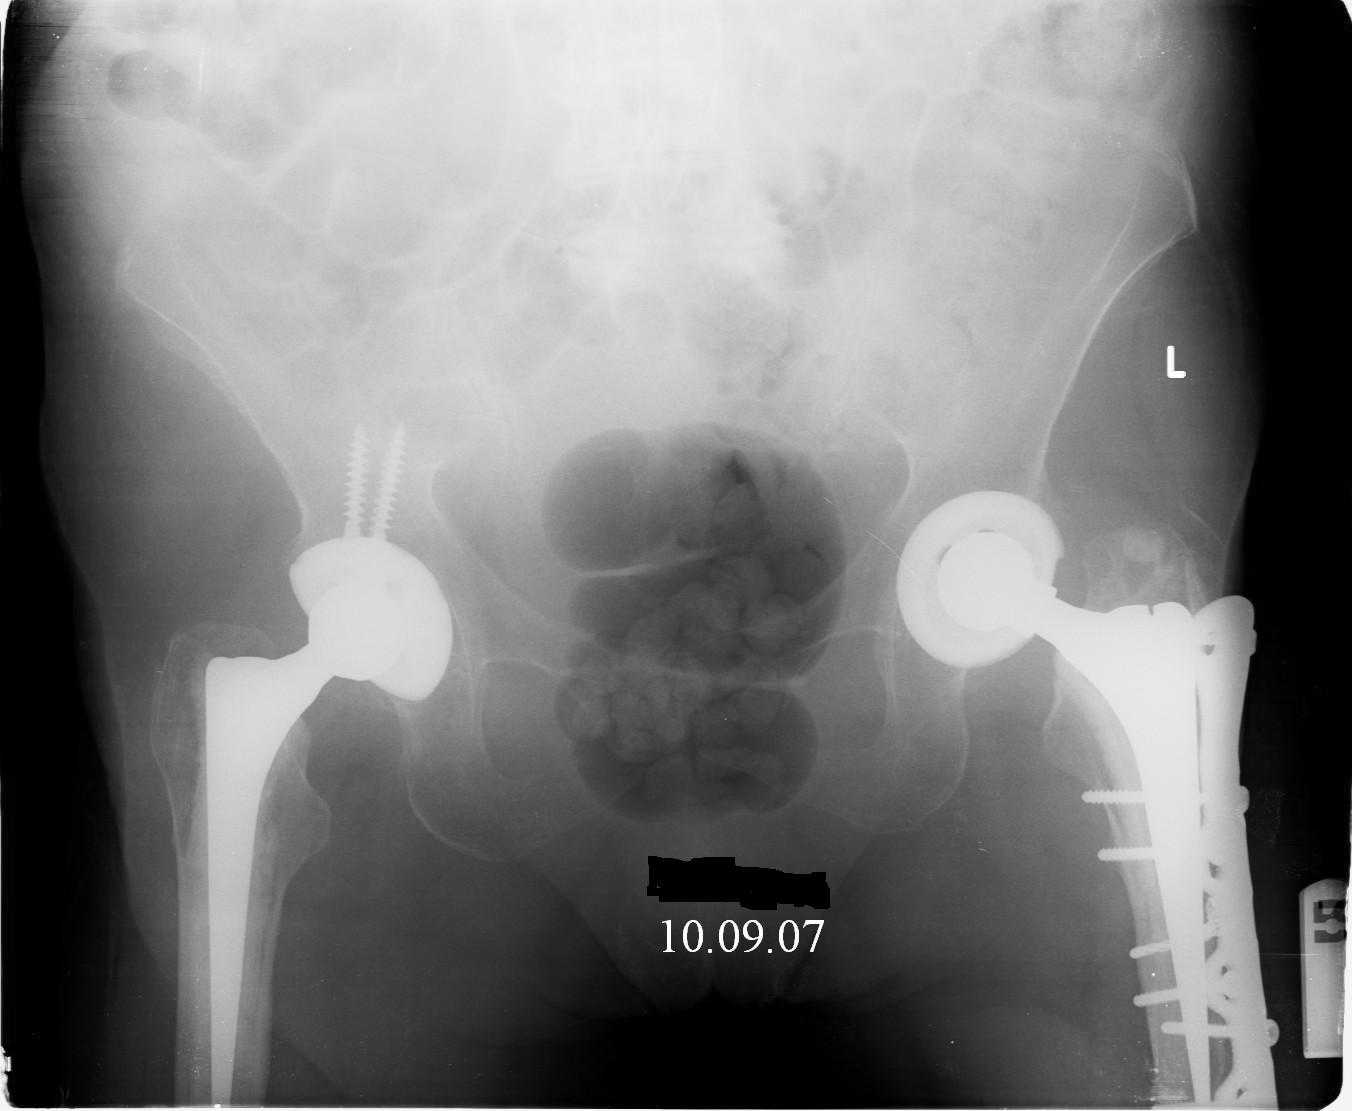

Although, there is just one view, it seems that cement is still holding well on lateral side, cup also seems to be stable, but inside is asymmetric – poly is damaged ... options:

Female, rheumatoid, THA in 2003, car accident in 2006, failed plating. Nailing in Oct 2007. The nail is solid with hollow proximal part where the stem is docked. Last images are in 1 year after

nailing.